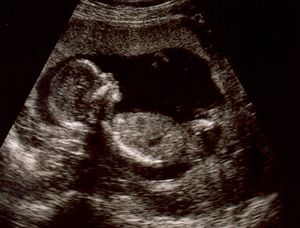

ينمو الجنين في هذا الأسبوع بشكل أكبر ويصبح حجمه في حجم حبة الفول ويصبح طوله 1.25 سم. يبدو شكل وحجم الرأس أكبر عن باقي حجم الجسم بشكل نسبي. ويستمر نمو الشكل الخارجي لتكوين أجزاء الوجه مع وجود بقع سوداء مكان العين وفتحتين صغيرتين جداً مكان الأنف وفتحة صغيرة جداً مكان الأذن. تبدأ براعم الأطراف في الظهور بشكل أوضح. تظهر اليدين والقدمين بشكل دائم الحركة وكأنها بدالات صغيرة.

تبدأ أيضاً الغدة النخامية وألياف العضلات في النمو في هذا الأسبوع. يبدأ القلب في النبض بشكل بسيط قد يكون غير مسموع بالنسبة لك ولكنه ينبض حوالي 150 نبضة في الدقيقة، وهو ضعف معدل النبضات الطبيعية لدى الشخص البالغ. يبدأ الطفل في منتصف الأسبوع السابع في القيام بأول حركة له، لكن لن تشعري بهذه الحركات إلا في المرحلة الثانية من الحمل (من 3 – 6 شهور).